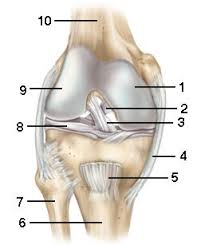

| 1. medial condyle 2. posterior cruciate ligament 3. anterior cruciate ligament 4. tibial collateral ligament 5. patellar ligament 6. tibia 7. fibula 8. lateral meniscus 9. lateral condyle 10. femur |